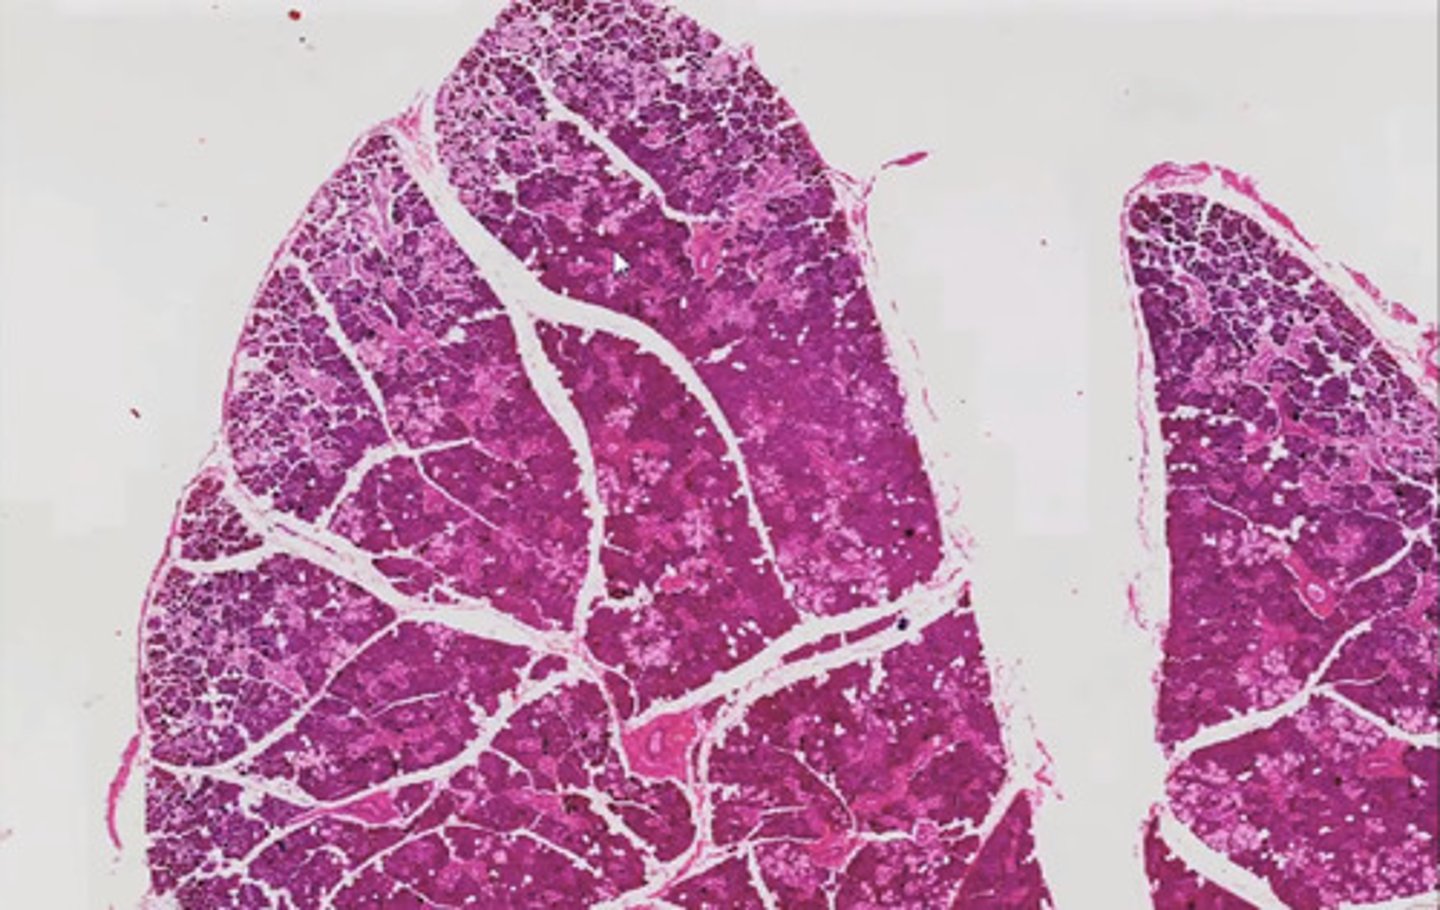

Miąższ płucny (H+E)

Miąższ płucny (orceina)